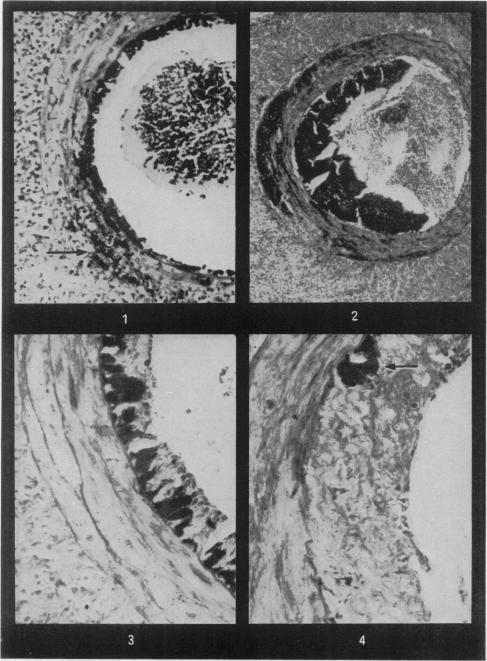

Lesions of the aorta and large muscular arteries were examined in experimental hypertension of the albino rat. In contradiction to the published data the earliest hypertensive lesion was a small artery type subendothelial fibrinoid and necrosis of single smooth muscle cells in the media and not an intimal thickening. In the large vessels such changes developed only after long periods of hypertension. No lesion corresponding to the media fibrinoid of small vessels was found in the large muscular vessels or in the aorta, owing apparently to inhibition of a greater penetration of plasma by the elastic fibres. This barrier role may in addition account for the absence of perivascular granulation around the aorta. In a later stage of the process, macrophages appeared in the subendothelial fibrinoid, phagocytosed it, and gave rise to intimal proliferation analogous to the intimal thickening in small vessels.

在白化大鼠实验性高血压模型中,对主动脉和大型肌性动脉的病变进行了检查。与已发表的数据相反,最早出现的高血压病变是小动脉型内皮下纤维蛋白样变性以及中膜单个平滑肌细胞坏死,而非内膜增厚。在大血管中,此类变化仅在高血压持续很长时间后才会出现。在大型肌性血管或主动脉中未发现与小血管中膜纤维蛋白样病变相对应的病变,这显然是由于弹性纤维对血浆更大穿透的抑制作用。这种屏障作用可能还解释了主动脉周围缺乏血管周围肉芽组织的原因。在病变后期,巨噬细胞出现在内皮下纤维蛋白样物质中,将其吞噬,并引发类似于小血管内膜增厚的内膜增殖。